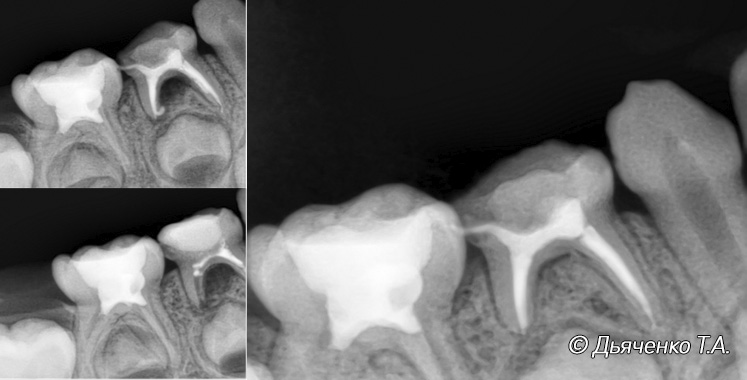

Длительный хронический периодонтит, острый периодонтит молочного зуба часто являются следствием обширного воспаления, ранней инфекционной резорбции корней молочных зубов более чем на ½. Все это является показанием к удалению таких зубов. При остром процессе удаление может быть сочетано, строго по назначению врача, с приемом медикаментозных препаратов (антибиотики, антигистаминные препараты и т.д.).

Основным лечением периодонтита молочного зуба является удаление. Необходимо защитить развивающийся зачаток постоянного зуба под ним от распространяющейся инфекции.

Если выявление периодонтита специалистом произошло на ранней стадии его развития и у ребенка хорошая кооперативность. Врач иногда может пролечить такой зуб, с условием строгого соблюдения профилактических-диагностических визитов для наблюдения за заживлением воспалительных процессов.